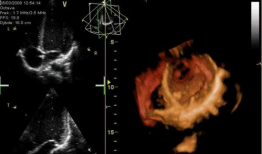

心脏跳动的视频,揭秘心脏跳动的奥秘

你知道吗?最近在网上流传着一个特别神奇的视频,它记录了心脏跳动的瞬间。这可不是普通的视频,它让我们仿佛能感受到心跳的力量,那种感...